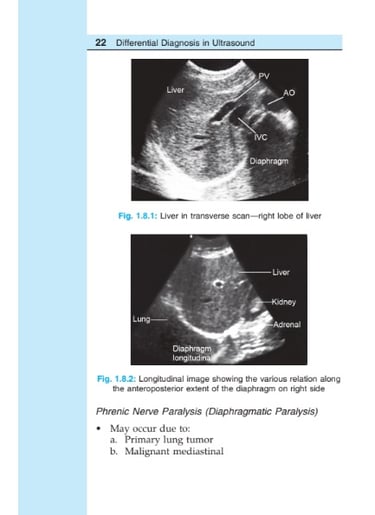

Differential Diagnosis in ULTRASOUND

Ultrasound is a noninvasive, relatively inexpensive and most rewarding imaging modality, carries no radiation

burden, but not much exploited for evaluation of chest disease because of basic (inherent) properties of US waves not to pass through bony cage and air-filled lungs. However, over a couple of years, US has emerged as a useful tool in evaluating wide range of perplexing clinical problems of chest due to presence of fluid in pleural space, consolidating or atelectatic lung or even tumor, provide window for US to penetrate and this has helped in diagnosis of certain conditions or limit the DD of conditions under consideration.